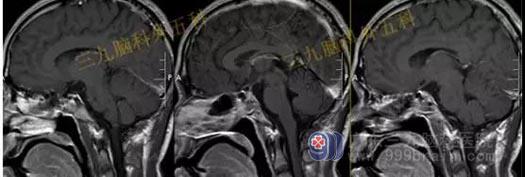

术前头部MR检查结果:鞍区示一团块状占位性病变,T1WI呈略低信号,T2WI呈稍高信号,增强后呈明显强化,病变界限清晰,边缘光整,范围约为3.1cm×2.7cm×2.0cm。病变示明显束腰征,垂体柄及视交叉受压显示不清,邻近颈内动脉受压移位,部分被包绕。

结果:鞍区垂体大腺瘤;病变部分包绕邻近颈内动脉。

手术过程:内镜下经鼻蝶鞍区垂体大腺瘤切除术,术中磨除鞍底,先行瘤内减压,双吸引器有序切除肿瘤,垂体及鞍隔保护良好,无脑脊液漏形成,肿瘤全切。

术后头部MR检查提示:肿瘤已全切。